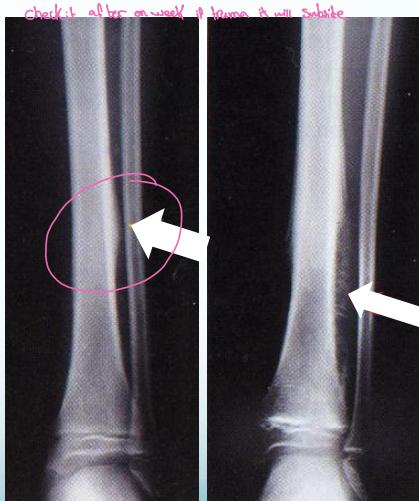

Case Example:

- 12-year-old girl

- History of trauma

- Mild tenderness

- Periosteal reaction

- Initially diagnosed as injury

- 2 months later, still tender

- Final diagnosis: Ewing’s sarcoma